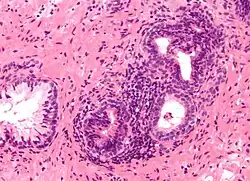

Microanatomia

A próstata consiste em tecido glandular e conjuntivo. Células altas em forma de coluna formam o revestimento (o epitélio) das glândulas.[1] Estas formam uma camada ou podem ser pseudoestratificadas.[3] O epitélio é altamente variável e áreas de células cuboidais baixas ou planas também podem estar presentes, com epitélio transicional nas regiões externas dos ductos mais longos.[9] As glândulas são formadas como muitos folículos, que drenam para os canais e, subsequentemente, para 12–20 ductos principais. Estes, por sua vez, drenam para a uretra à medida que passa pela próstata.[3] Há também uma pequena quantidade de células planas, que ficam próximas às membranas basais das glândulas e agem como células-tronco.[1]

O tecido conjuntivo da próstata é composto de tecido fibroso e músculo liso. O tecido fibroso separa a glândula em lóbulos.[1] Ele também fica entre as glândulas e é composto por feixes de músculos lisos orientados aleatoriamente que são contínuos com a bexiga.[10] Com o tempo, secreções espessadas chamadas corpora amylacea se acumulam na glândula.[1]

Glândulas microscópicas da próstata

Glândulas microscópicas da próstata